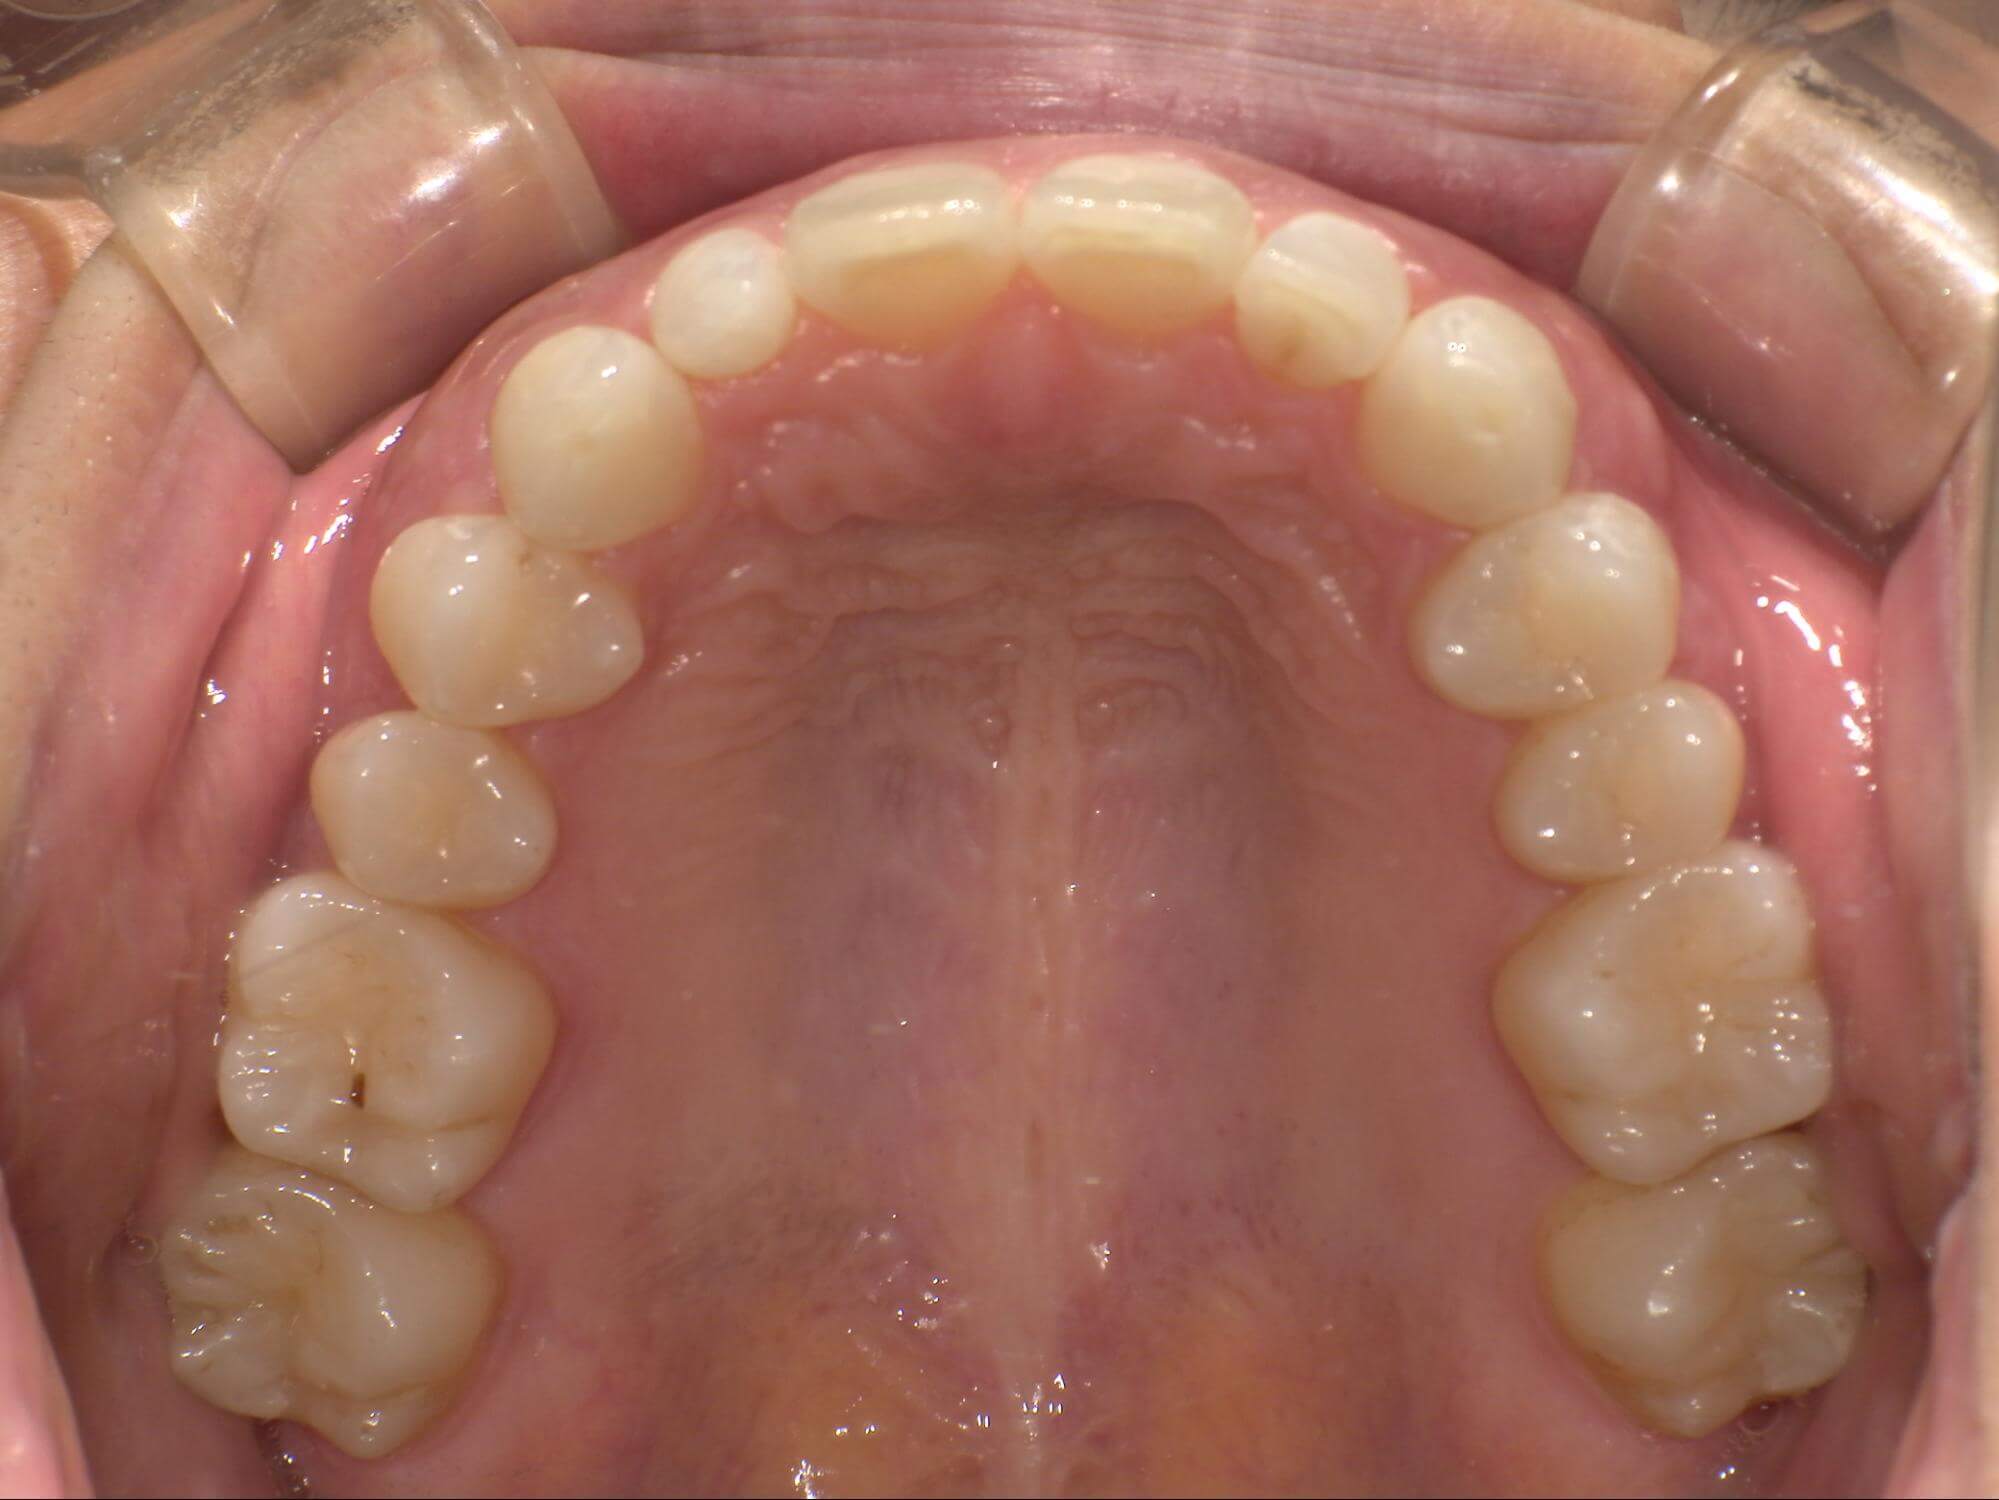

| 年齢・性別 | – |

|---|---|

| 主訴 | 叢生が気になる |

| 治療期間・回数 | 1年 |

| 費用 | 935,000円 |